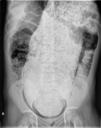

Con la sospecha de tumoración abdominal, y ante la imposibilidad de realizar ecografía abdominal, realizamos una radiografía de abdomen que evidencia megarrecto con abundante materia fecal de pelvis a epigastrio (fig. 2).